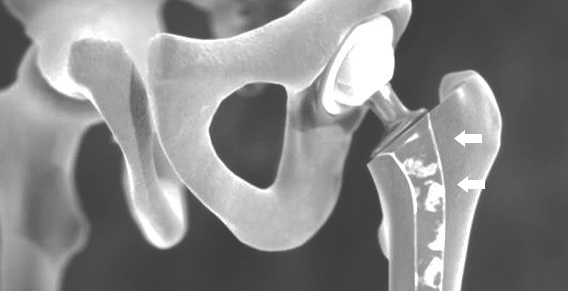

At the hip joint, infection of the prosthetic material, early subsidence of the shaft, or a fracture of the bone with involvement of the implants are particularly feared complications.

Often, a primary hip implant can be used for revision surgery. Sometimes, special revision implants are necessary.